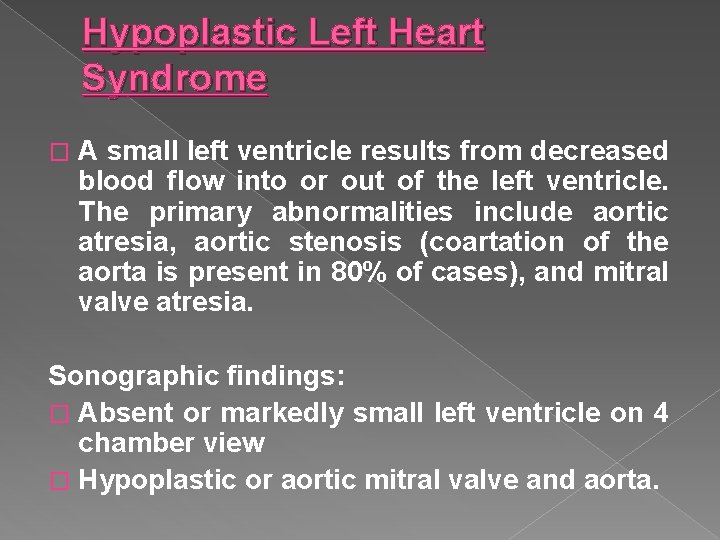

Hypoplastic Left Heart Syndrome � A small left ventricle results from decreased blood flow into or out of the left ventricle. The primary abnormalities include aortic atresia, aortic stenosis (coartation of the aorta is present in 80% of cases), and mitral valve atresia. Sonographic findings: � Absent or markedly small left ventricle on 4 chamber view � Hypoplastic or aortic mitral valve and aorta.

Hypoplastic left heart syndrome › Absent or markedly small left ventricle on a 4 chamber view. › Hypoplastic mitral valve and aorta

Hypoplastic Left Heart Ultrasound